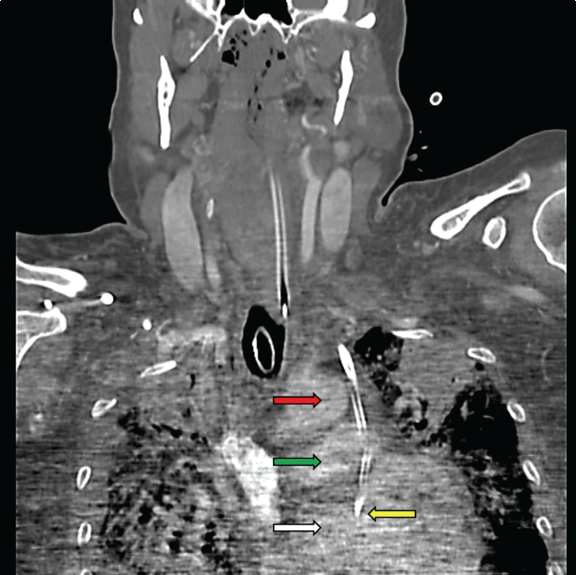

Figure 3: Computed tomography of the chest: Catheter (yellow arrow) noted millimeters from puncturing the aorta (red arrow), traversing the pulmonary artery (green arrow), and entering the left atrium (white arrow).